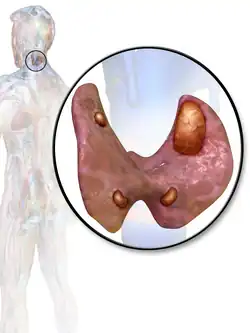

| 3D diagram of hyperparathyroidism | |

The parathyroid is composed of 4 glands with 2 located superiorly and 2 located inferiorly.[23] The parathyroid glands are located on the posterior thyroid and are derived from the endoderm of the 3rd and 4th pharyngeal pouches.[23] Specifically, the inferior parathyroid glands are derived from the 3rd pharyngeal pouch and the superior parathyroid glands are derived from the 4th pharyngeal pouch dorsal wing.[24] The ultimopharyngeal body is derived from the 4th pharyngeal pouch ventral wing and the parafollicular cells ( C-cells) are derived when the ultimopharyngeal bodies fuse with the posterolateral thyroid.[24] The parathyroid glands separates from the pharyngeal wall and attaches to the posterior thyroid during the 7th week of human embryonic development.[23]